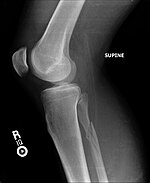

Hill–Sachs fracture Harold Arthur Hill

Maurice David Sachs

impacted posterior humeral head fracture occurring during anterior shoulder dislocation Hill Sachs Lesion Archived 2020-09-20 at the Wayback Machine at Wheeless' Textbook of Orthopaedics online Dislocated shoulder X-ray 03.png